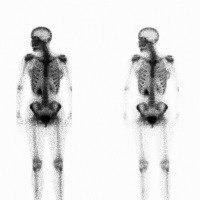

Scintigrafi er en undersøkelse der kroppen tilføres små mengder radioaktive stoffer (isotoper). Undersøkelsen foregår i to etapper. Først sprøytes de radioaktive stoffene direkte inn i blodet. Disse stoffene er laget slik at de først og fremst konsentreres i de organene i kroppen man ønsker å undersøke (f.eks. skjelettet). Dette kan ta noe tid, slik at det er ventetid mellom innsprøytingen av isotopene og bildeopptaket. Ved hjelp av et apparat som registerer den radioaktive strålingen fra stoffene (gammakamera), dannes det et bilde - et scintigram. Bildet er en samling punkter og gir ikke noen presis fremstilling av de organene som studeres, men informasjonen kan være til stor nytte for å løse ditt medisinske problem.

Ved skjelettscintigrafi brukes et radioaktivt merket kjemisk stoff som inneholder fosfat. Etter at stoffet er sprøytet inn i blodet, tas det opp av kroppens bein. Ekstra store konsentrasjoner av disse isotopene vil finnes i beinområder med økt blodtilførsel og høy aktivitet i forbindelse med nedbryting og oppbygging av bein. Dette vil være områder hvor det foreligger en sykdom eller en skade. Testen anvendes særlig til påvisning og oppfølging av kreftspredning til skjelettet (skjelettmetastaser). Særlig brystkreft, prostatakreft, lungekreft og lymfekreft vil kunne spre seg til bein.

Skjelettscintigrafi kan påvise sykelige forandringer opptil 6-12 måneder før de synes på røntgen. Testen brukes også i diagnostikken av en lang rekke andre tilstander. Den kan også brukes til å tidfeste og synliggjøre reparasjonen av skader og betennelsesreaksjonen ved infeksjoner. Ved en normal undersøkelse er de radioaktive stoffene jevnt fordelt i skjelettet og det finnes ikke områder eller flekker med store konsentrasjoner.